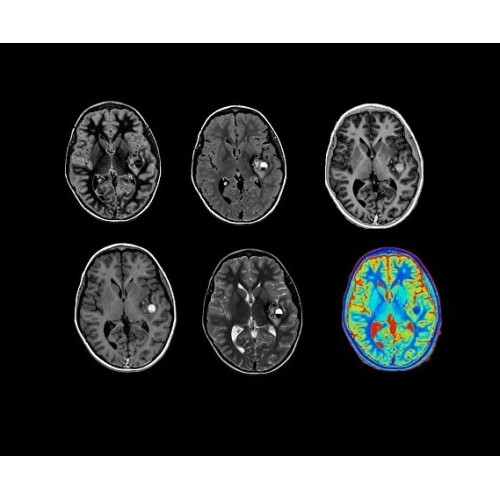

SIGNA Architect 3.0T — это новейший МРТ аппарат компании GE, который предлагает высочайший уровень производительности — в системе 128 приемных каналов, 48 канальная катушка головы, полный спектр клинических возможностей. Высокий уровень комфорта пациента обеспечивают такие особенности как отсоединяемый стол, положение пациента «ногами вперед» для всех видов исследований, SilentWorks — бесшумное и MAGIC — быстрое сканирование.

Теперь возможности МРТ поражают еще больше благодаря ультрасовременным решениям для визуализации с SIGNA Architect 3.0 Тл, объединяющей новейшие достижения в области МР-технологий и интуитивно понятный интерфейс. Система SIGNA Architect, разработанная на базе новой платформы SIGNA Works, представляет собой гармоничное сочетание дизайна и функциональности. Каждый элемент системы направлен на повышение производительности, эффективности клинической практики, финансовых показателей, а также комфорта и безопасности пациента.

Поле обзора 50x50x50 см и апертура шириной 70 см позволят достоверно визуализировать сложные анатомические области для пациентов с крупным телосложением, например, плечи и бедра. Феноменальная однородность системы SIGNA Architect обеспечивает наиболее широкое поле обзора с улучшенными характеристиками градиентов. Ничто не останется незамеченным.

Стандартный пакет приложений SIGNA Works позволит вам достичь желаемых результатов в клинической практике благодаря набору высокоэффективных средств визуализации. Программные приложения, входящие в состав данных клинических пакетов, включают широкий спектр контрастов, функции обработки 2D- и 3D-данных, а также возможность коррекции артефактов движения. SIGNA Works предоставляет набор инструментов, необходимых для проведения эффективного клинического исследования.

• NeuroWorks — универсальное решение для визуализации анатомии головного мозга, позвоночника, сосудов и периферических нервов с четкой дифференциацией тканей.

• ImageWorks — повысит производительность МРТ благодаря визуализации высокого качества с MAGIC, четкими результатами пост-процессинга с READYView.

• 48-канальная катушка TDI для головы, входящая в базовую комплектацию SIGNA Architect, обеспечивает феноменальную производительность с учетом особенностей каждого пациента. Благодаря гибкому и универсальному дизайну, высокому соотношению сигнал/шум и передовым технологиям визуализации, таким как HyperWorks, учитываются потребности подавляющего большинства пациентов.